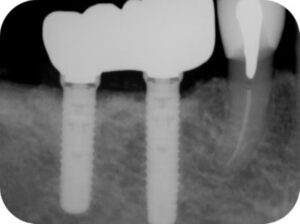

治療後8年が経過しましたが、定期健診においても周囲炎の再発もなく順調に推移しています。

この患者様の場合、口腔内清掃の重要性の理解と実践が治療結果に大きく関係しているものと考えています。

今後も気を緩めることなく、二人三脚でメンテナンスに取り組んでいきたいと考えています。